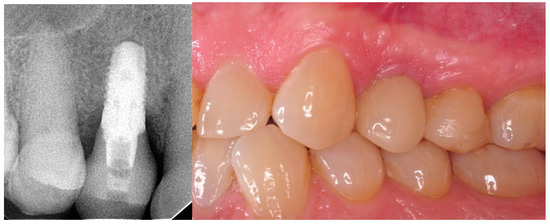

- Implantation: intraoperative and postoperative RVG (radiovisiography—Planmeca OY, Helsinki, Finland), gingival biotype assessment thick/thin;

- Four weeks after the implantation: intraoral scan, screw-retained prosthetic, RVG;

- Twelve months after the surgery: clinical evaluation (HKT, probing pocket depth (PPD), Visual Analogue Scale (VAS), pink esthetic score (PES) and white esthetic score (WES)) and radiological assessment (RVG and CBCT).